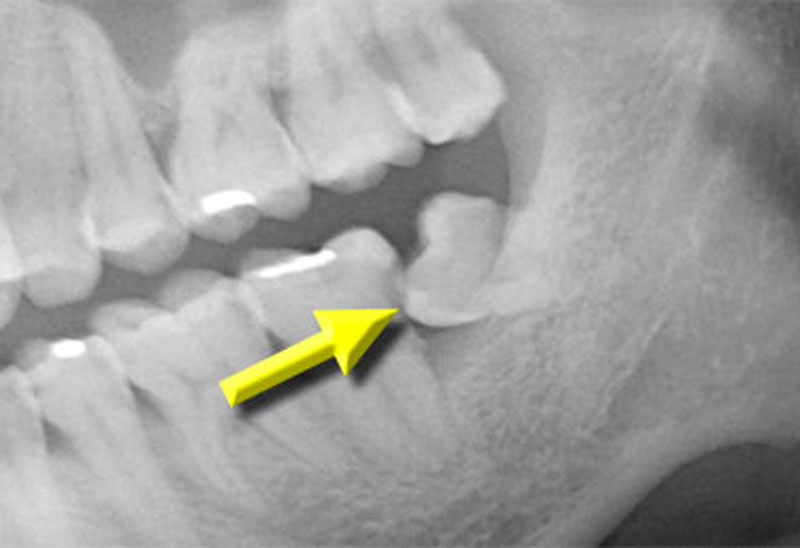

智齒不只造成牙周病,同一顆智齒也造成鄰接的第二大臼齒蛀牙,箭頭指的黑色部分就是被蛀空的牙齒。